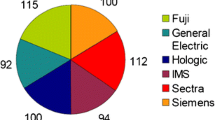

Supplementary Fig. 2 Mediolateral oblique (MLO) views of mammogram examples(a) and automated breast composition assessment(b) by Volpara®. Two mammogram examples of the same patient taken at Shizuoka Cancer Hospital and the evaluation of breast composition using automated software Volpara® are shown. Automated software evaluated Volumetric Breast Density at 10.2% and classified the breast composition as grade c.